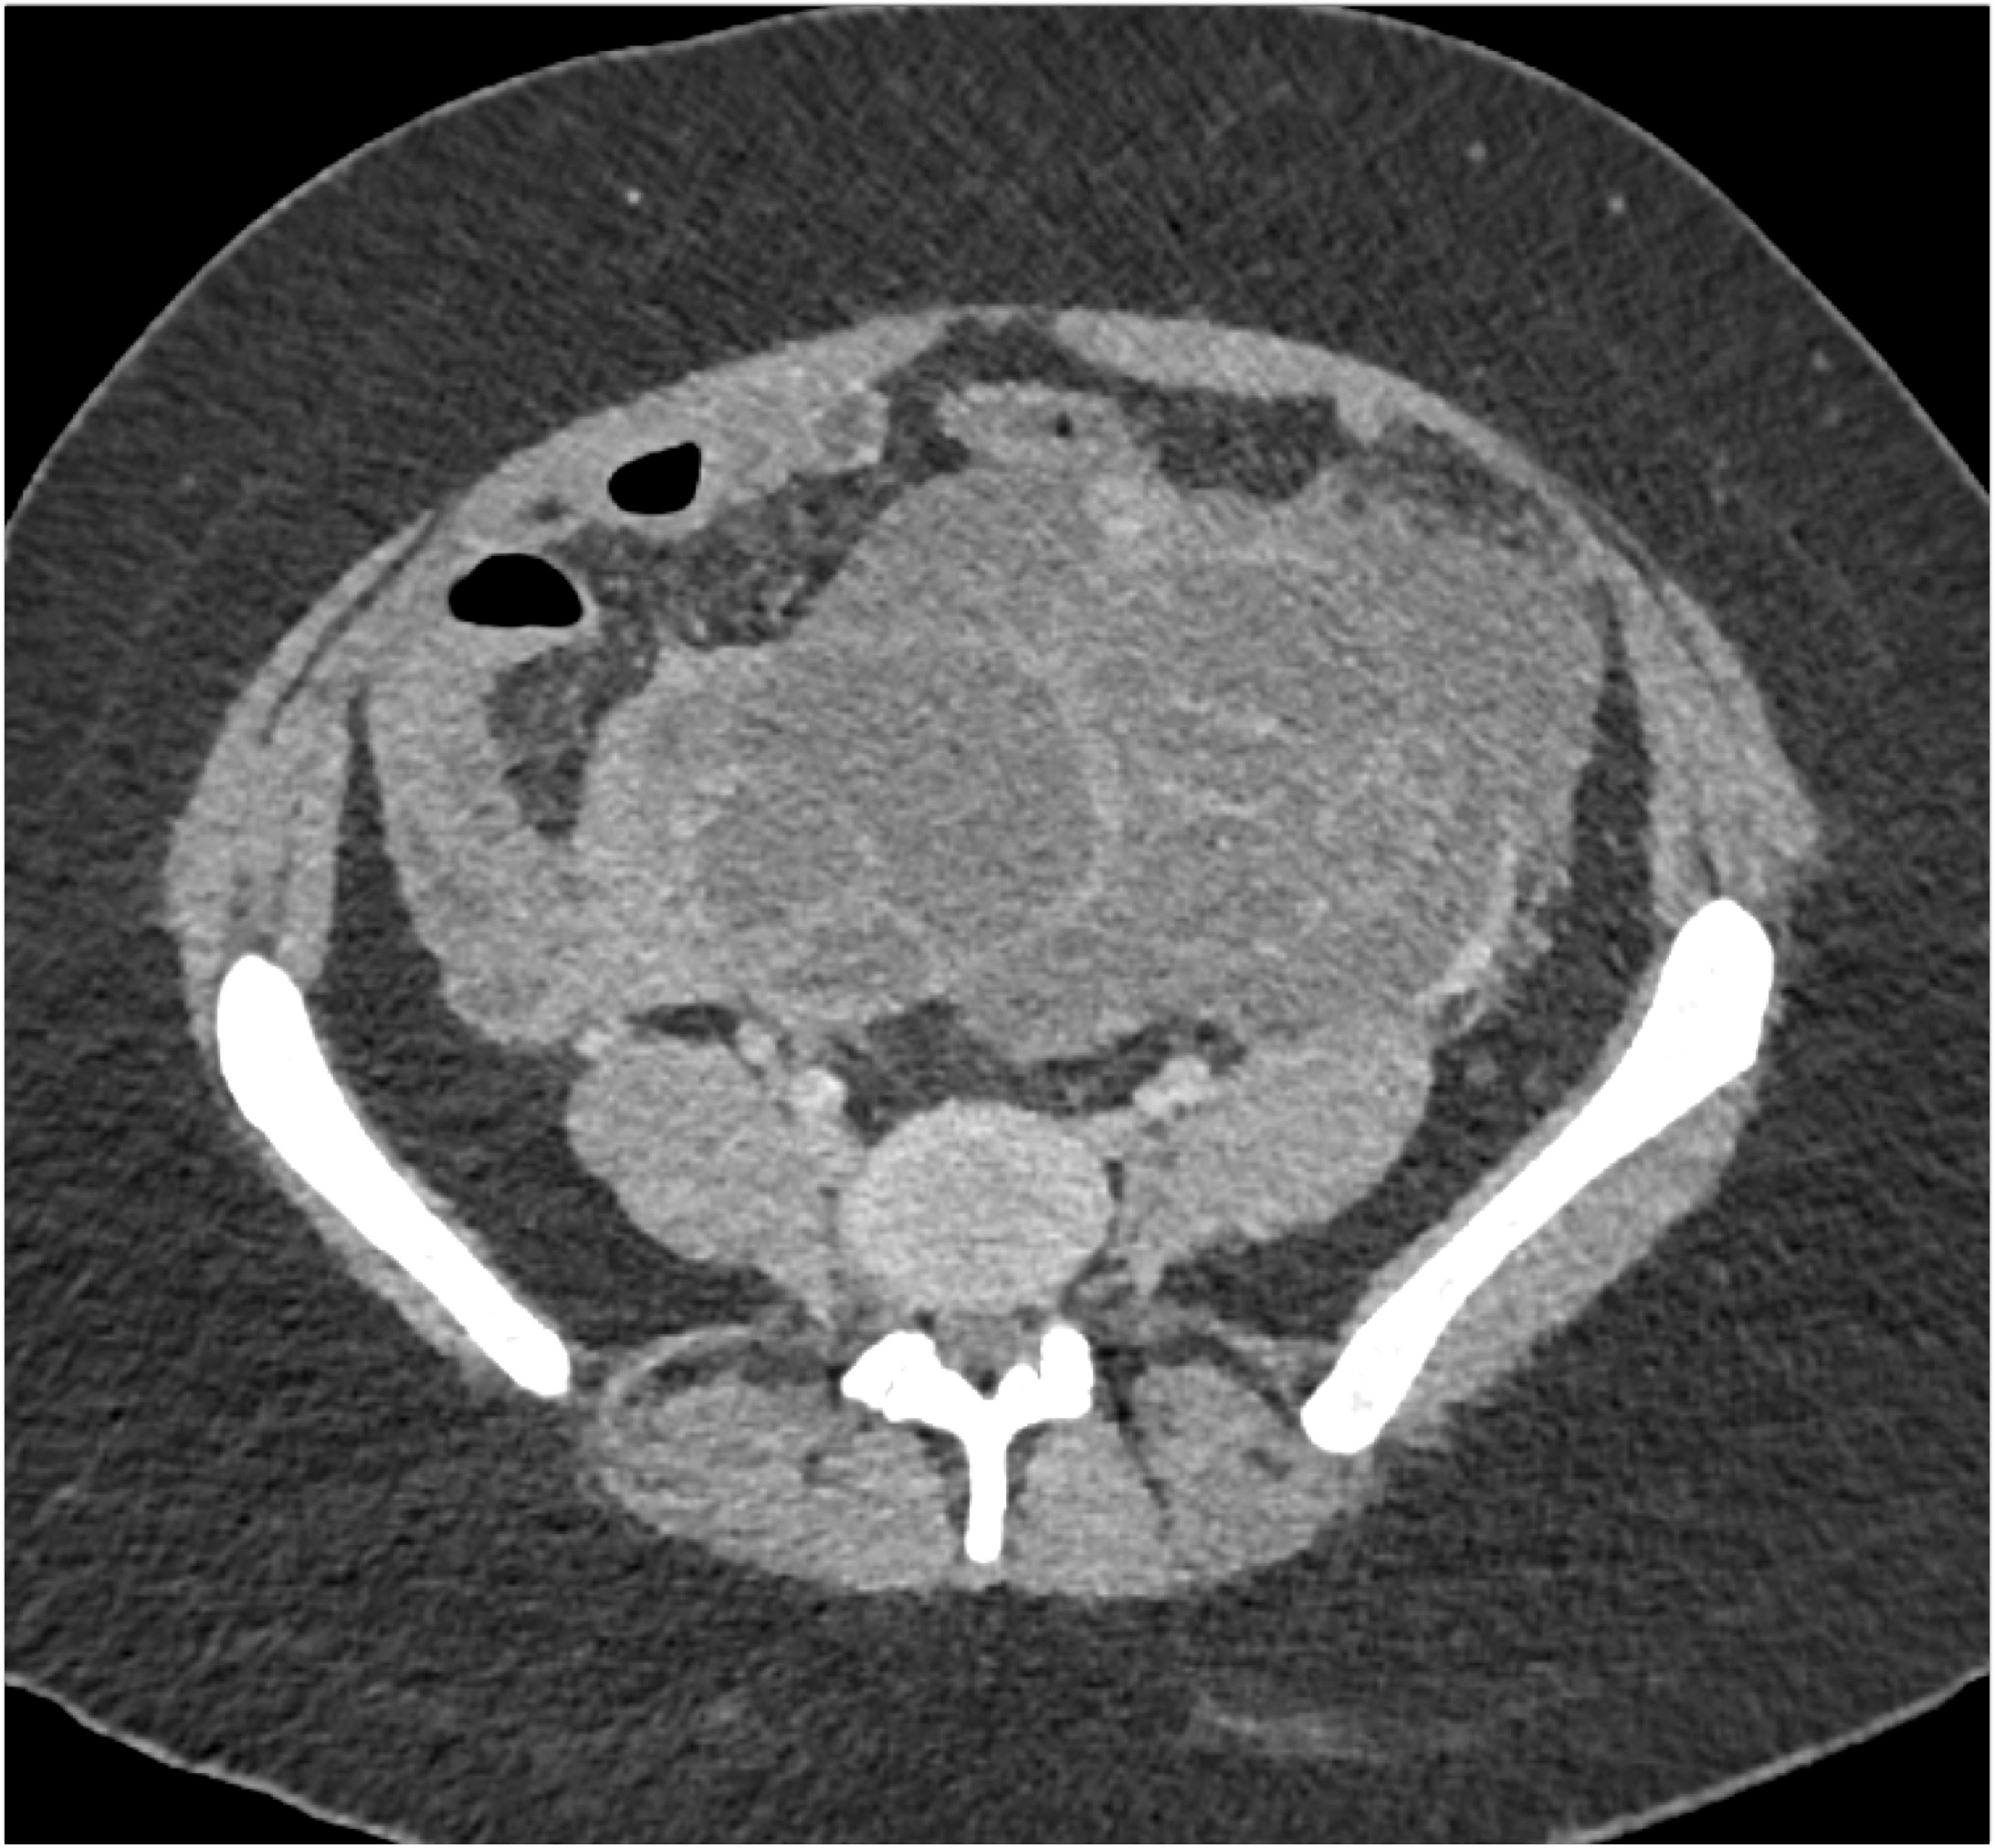

- Evaluate the CT images of each question carefully.

- Take time to make the call on the diagnosis for each individual question.